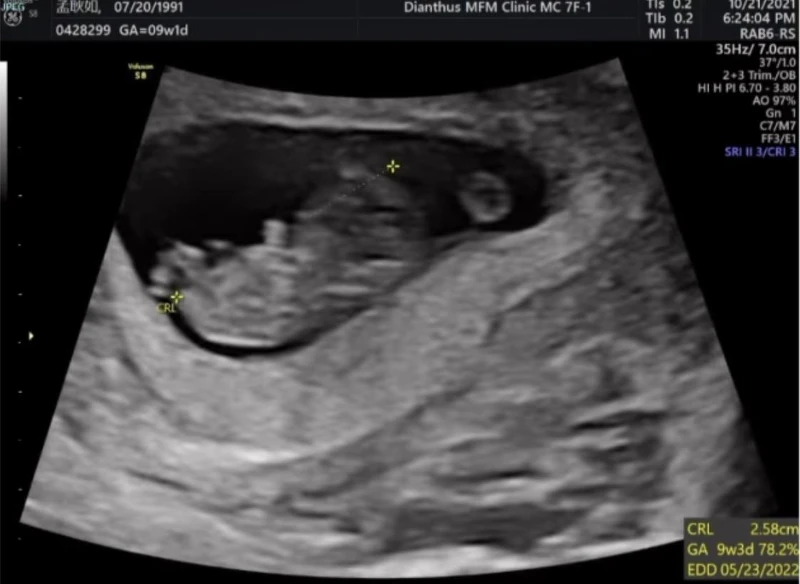

孟耿如在臉書寫下:「終於~~~可以開心的跟大家分享這個消息,目前不知道是小黃瓜還是黃玉米已經在肚子裡三個月了,上面的超音波影片是兩個月的時候他的小手手在跟我們打招呼。」

她也表示肚子裡現在有個六七公分的生命真的很神奇:「懷孕到目前一次孕吐都沒有,醫生說我很適合懷孕哈哈哈,但賀爾蒙導致心情沮喪低落是讓我目前覺得最辛苦的地方,不過大家別擔心,老公和朋友都有盡力拉我出門走走,曬曬太陽運動運動,然後醫生有一直提醒我懷孕不是生病,平常生活是如此就盡量維持,所以我還是很活躍的,唯一一點!在此喊話各位廠商或電視台不要讓我老公太忙,他時常早出晚歸我一個人比較孤單一些,早早放他回家好嗎?或現在開始不要找他工作,找我可以,哈哈哈哈哈。」